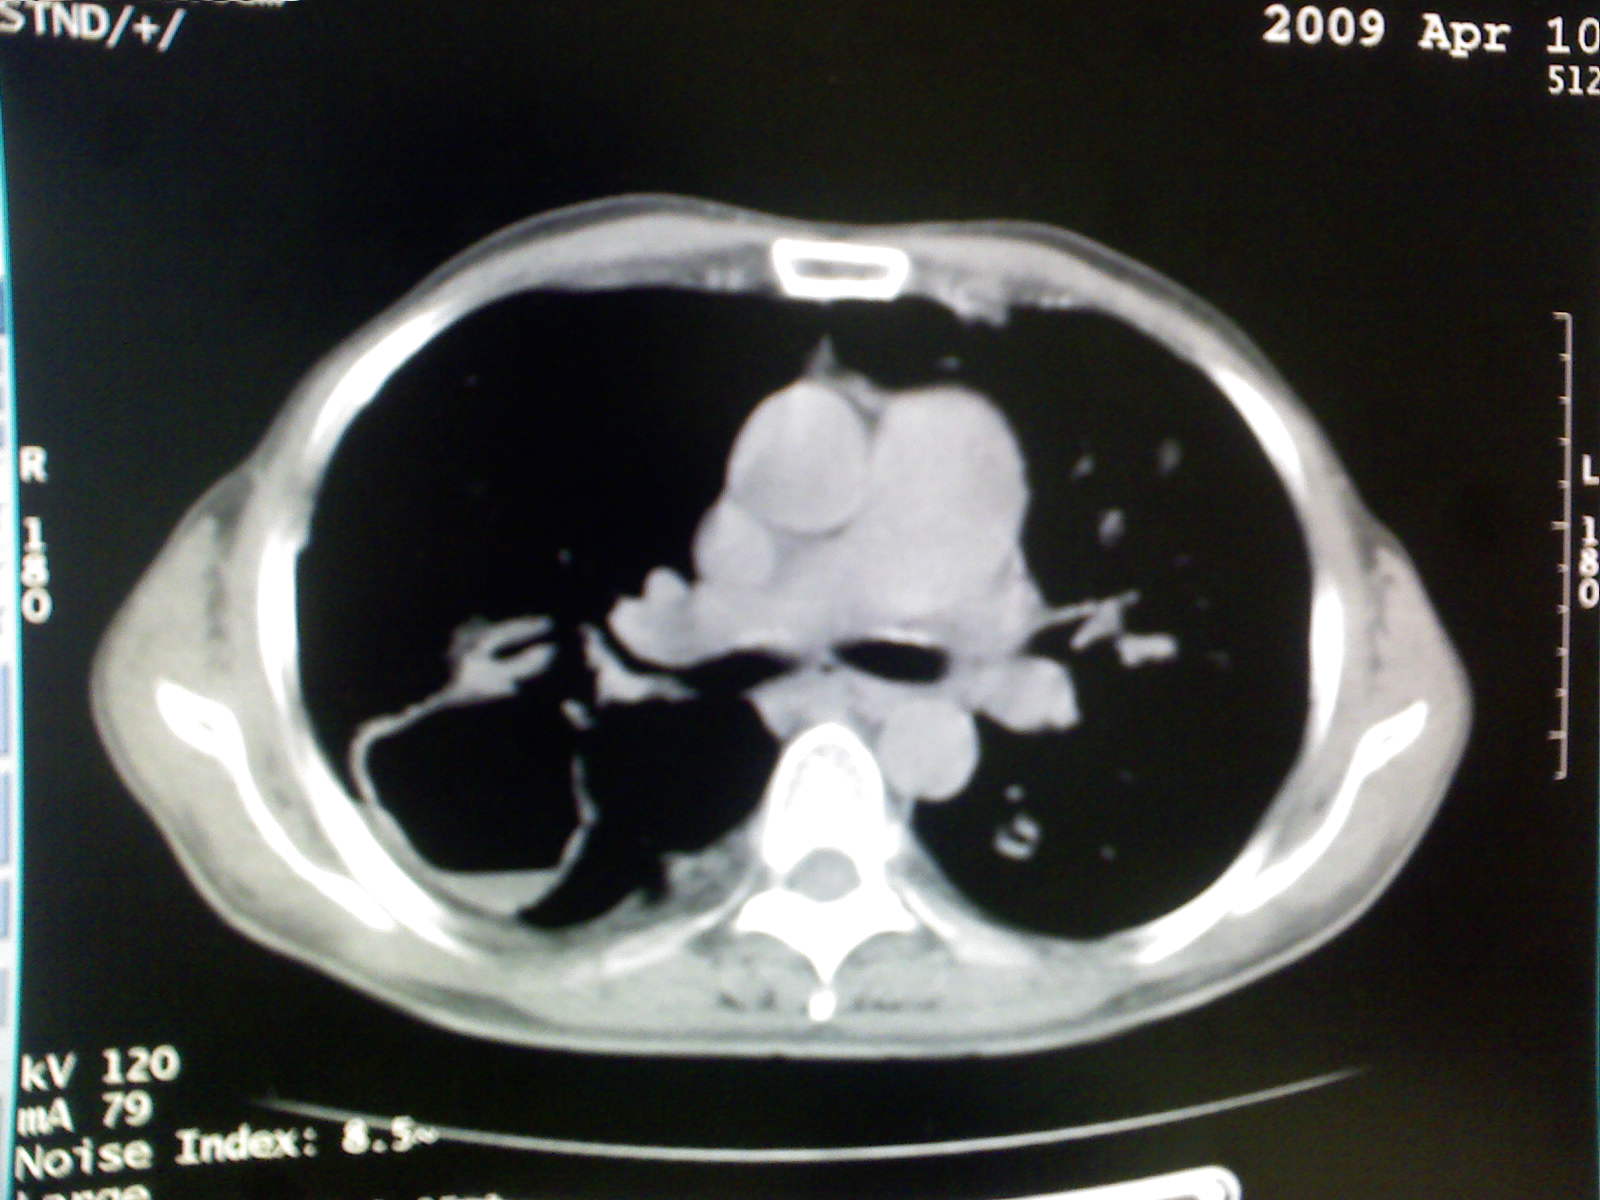

以下是引用卜一在2009-4-11 15:50:00的发言:[br]双肺继发性肺结核伴空洞形成,不排除合并霉菌感染!(病灶呈多形态 多特征 散在分布)。另:合并支气管扩张征伴感染!

以下是引用主力军在2009-4-11 15:55:00的发言:[br]两肺继发性肺结核可能性大。

以下是引用康鹏在2009-4-11 16:30:00的发言:[br]双肺继发性肺结核伴空洞形成合并感染[br]支气管扩张合并感染